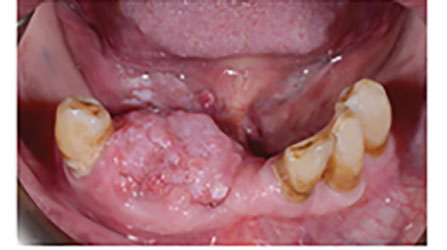

Oral Cancer: Screening and Early Discovery

oral cancer

A vast amount of my career has been spent on defining our powerful role as dental hygienists in the earlier discovery of an abnormal lesion through effective visual and tactile examination of the structures of the head, neck and oral cavity. Frankly, the omission of a thorough and effective extraoral/intraoral examination can cost a life. … Read more